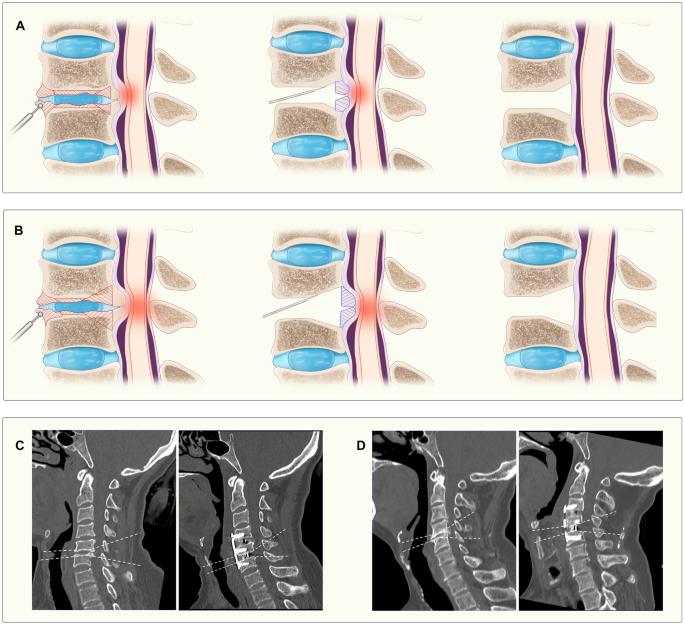

The patient was placed in the supine position after anesthesia. A transverse incision was made on the right side of the neck, and the platysma muscle was freed and stretched to both sides to expose the cervical vertebrae. Fluoroscopy was used to confirm the correct level of surgery. As shown in Fig. 1, the HSD was first used to remove the anterior cervical osteophytes, to expose as much of the intervertebral disc space as possible, and to create a flat edge of the vertebral body for placement of the titanium plate. The disc was completely removed under the operating microscope, and a portion of the cartilage endplate was removed using the HSD. The depth of drilling was determined by the size of the osteophytes (Fig. 1). When the osteophytes were small, they do not exceed the concavity of the cartilage endplate, the drill was directed 3/4–4/5 into the intervertebral space, and the UBS was used to cut the osteophytes parallel to the endplate. When the osteophytes were large and exceeded the concavity of the cartilage endplate, the drill was directed 1/2–2/3 into the intervertebral space. Subsequently, a small portion of the posterior vertebral body and the medial Luschka joint was removed using the HSD to form a sharp bone groove to facilitate the UBS operation without slippage (Fig. 2). The osteophytes were then completely severed with the UBS along the bone groove. Then, the UBS was used to completely cut the osteophytes obliquely upward or downward. Finally, the osteophytes were carefully removed under the protection of a nerve dissector. If the osteophytes were too large to be removed, they could be cut into pieces by UBS and removed out separately (Fig. 2).

Illustration of surgical procedure using UBS to remove osteophytes and illustrative case presentation. (A,B) Illustrates different strategies for small and large osteophytes. The red area within the vertebral body represents the region that requires abrasion by the high-speed drill, and the blue area represents the region that are removed with the ultrasonic bone scalpel. Figures (C,D) depict preoperative and postoperative assessments of small and large osteophytes, respectively, with the dashed line illustrating the cutting trajectory of the ultrasonic bone scalpel.